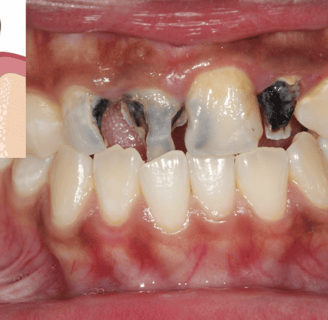

It can be caused by a variety of factors, including cavities, tooth decay, gum disease, and injuries.

Cavities: Cavities are holes in the teeth that are caused by plaque buildup. Plaque is a sticky film of bacteria that forms on the teeth. When plaque is not removed, it can produce acids that attack the tooth enamel. This can lead to cavities, which can cause pain and sensitivity.

Tooth decay: Tooth decay is a process that causes the breakdown of tooth enamel and dentin. It is caused by a combination of factors, including plaque buildup, sugary foods and drinks, and poor oral hygiene. Tooth decay can cause pain, sensitivity, and tooth loss.

Gum disease: Gum disease is an infection of the gums. It is caused by plaque buildup and poor oral hygiene. Gum disease can cause pain, swelling, bleeding, and tooth loss.